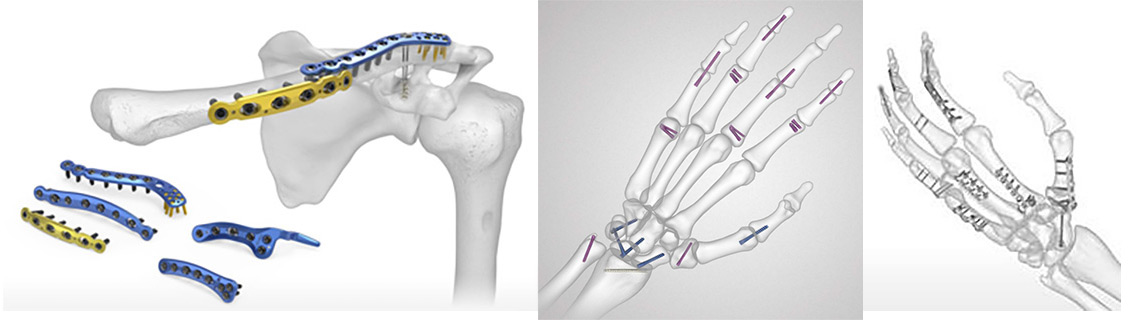

Fractura Mediodiafisaria de Clavicula: que hay de nuevo en 2025?

Estrategias actuales en fracturas de la mano: precisión, estabilidad y función.